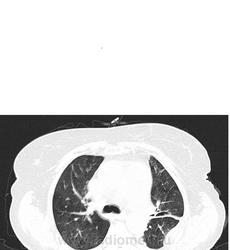

Мне видится хроническая ТЭЛА-упорно зрю мозаичность, видится сумасшедшая легочная гипертензия, застойные сердечные дела, и о ужас... мерещится мезотелиома... все эти узелки по плевре, каплевидны формы, прям по междолевочке... да и шарик в печени - али не гиповаскулярный метастаз???

ТЭЛА без контраста не исключишь. При таком гидротораксе добавил бы исследование на животе (или на боку, если ей это легче). Кстати, а почему сразу мезотелиома? А в легких застой и отек.

мезотелиома злокачественная сопровождается рецидивирующим большим гидротораксом, а доброкачественный вариант выглядит не так . Тут мне видится междолевой и костальный плеврофиброз , осумкавание жидкости по заднебоковой поверхности , возможно. На счет легких согласна с предыдущим мнением, хотя на счет отека у меня не повернулся бы язык.

шарик в печени , с предательски четкими и ровными контурами для метастаза, я за кисту. Осумкование выпота в плевральной полости может быть различное и по всякому, что там по плотности ? )))

По поводу сосудистой гиперволемии и интерстициального отека - он может выгледеть в виде матового стекла, но будет располгаться в гравитационно-зависимых зонах (то есть в задних отделах различных долей легких: паракостально, по ходу междолевых щелей), часто если есть гиперволемия то видно относительное расширение легочных сосудов - преимущественно за счет легочных вен и наличие ретикулярного паттрена - утолщение периферического субплеврального и междолькового интерсиция. Чтобы отличить воспалительыне изменения в задних субплевральных отделах от застойных - можно повернуть на живот. Но, по большому счету, делать этого не надо,

В вышеприведенном случае - явных КТ-данных за наличие отек - я не вижу.

По поводу жидкостных образований паракостально слева - на мой взгляд просто осумкование жидкости (но кто его точно знает...) Мехотелиома не исключена.

В печени больше данных за простую кисту.

Вообщим на мой взгляд - ХТЛГ возможно рецидив.